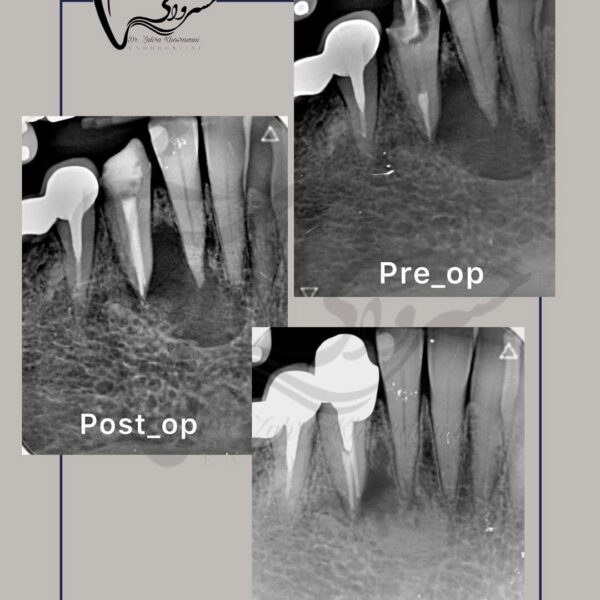

درمان ریشه مجدد

درمان ریشه مجدد دندان مولر دوم با ریشه رادیکس